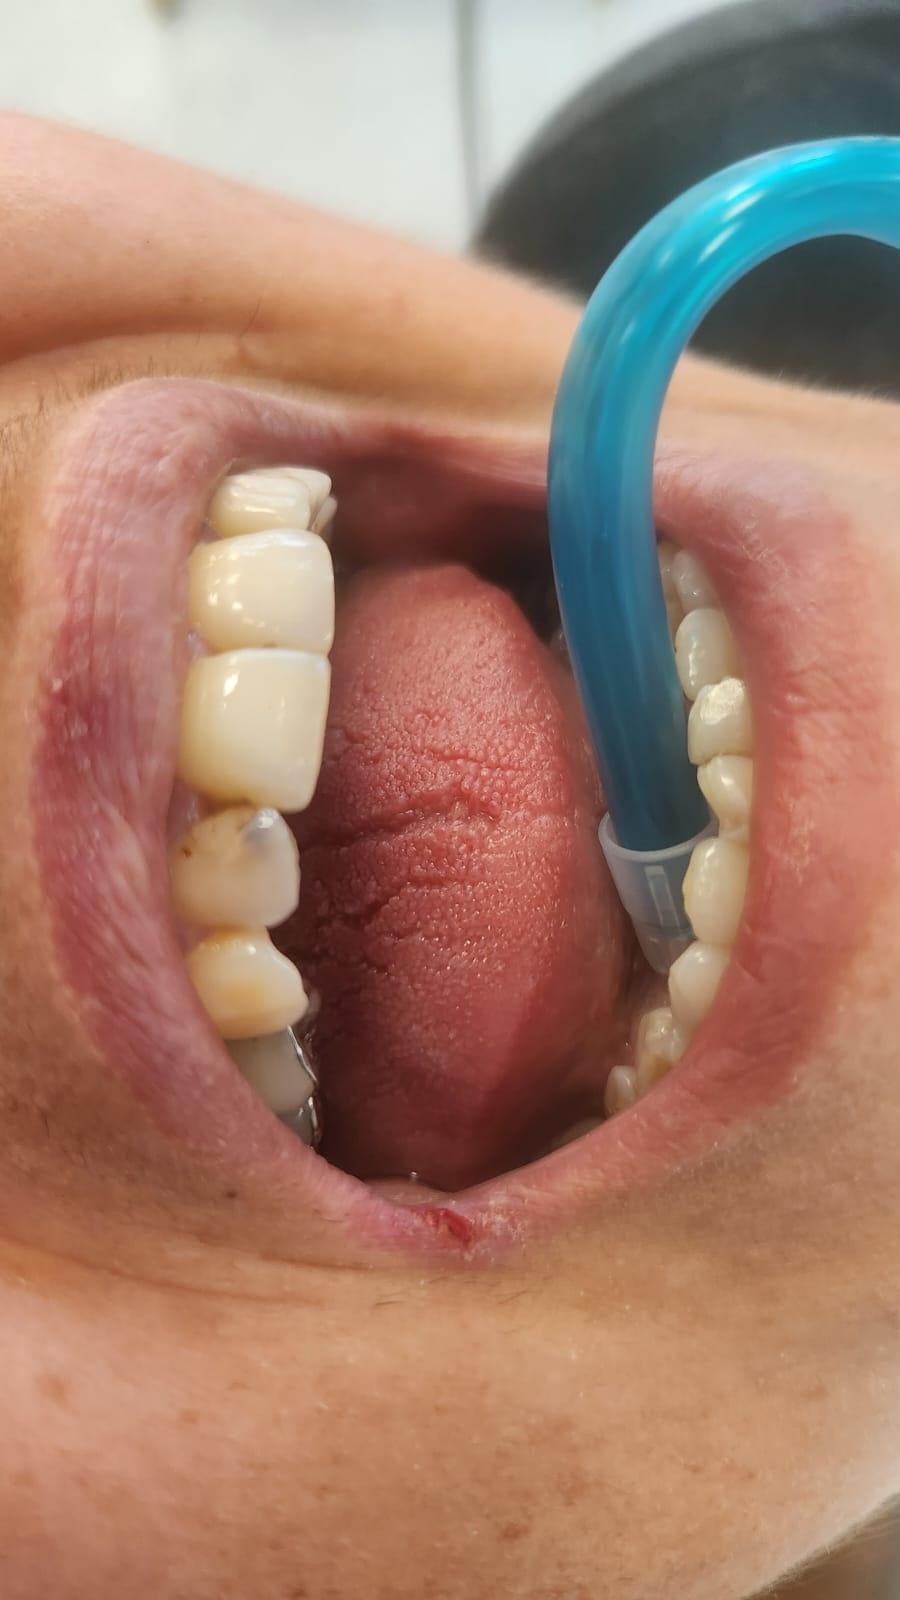

Clinica LUY ESTHETIC ART defineste parodontoza ca fiind rezultatul direct al placii dentare, care se depune pe suprafata dintilor, dar si in apropiere de marginea gingivala. Aceasta boala duce la pierderea dintilor, chiar daca ei sunt aparent sanatosi si nu prezinta carii. Edentatiile, afecteaza vorbirea, aspectul, dar si capacitatea de a mesteca.

Semnele aparitiei paradontozei:

– gingiile sangereaza la periaj;

– gingii rosii si inflamate;

– mobilitatea sau deplasarea dintilor;